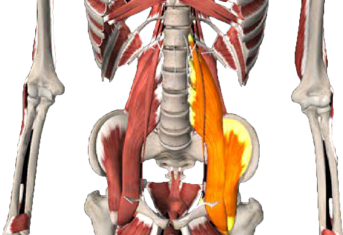

Als je schrikt, duik je automatisch in elkaar: je trekt je schouders op, je rug kromt zich als een soort schild. Een belangrijke beschermende spiergroep hierbij zijn de psoasspieren. Samen vormen deze spieren een systeem dat de romp, het bekken en de benen verbindt. De meeste sympathische zenuwen, waaronder de vecht- en vluchtzenuwen, bevinden zich in dit gebied. De psoasspieren ondersteunen de vecht- vluchtreactie van het menselijk organisme. Deze spieren zijn een soort van wachtposten in het centrum van het lichaam. Ze verbinden de rug met het bekken en de benen. Bij gevaar trekken de psoasspieren samen.

Samentrekkende psoasspieren laten het lichaam vooroverbuigen. Gespannen of beschadigde psoasspieren kunnen hevige pijn in de onderrug veroorzaken. Dit komt bijvoorbeeld veel voor bij mensen die seksueel misbruikt zijn. Secundaire rugpijn of beenpijn ontstaat hier veelal bij, doordat het lichaam probeert de voorwaartse trek van het lichaam te compenseren. De lange rechte rugspieren trekken het lichaam naar achter in een poging het staande te houden. Hierdoor ontstaat er spanning op de ruggenwervel, wat op den duur chronische schouder- en nekklachten tot gevolg kan hebben. Daarnaast kan de middenrifspier ook spanning in dit gebied veroorzaken.

Om te herstellen van fysieke traumatische spanningen moeten vooral de diepliggende psoasspiergroep, de spieren waarmee je de rug strekt (de erector spinae) en de schouder- en nekspieren hun defensieve spanning weer loslaten en terugkeren in de ontspannen toestand.

5. Vierhoekige lendenspier

6. Grote lendenspier en darmbeenspier